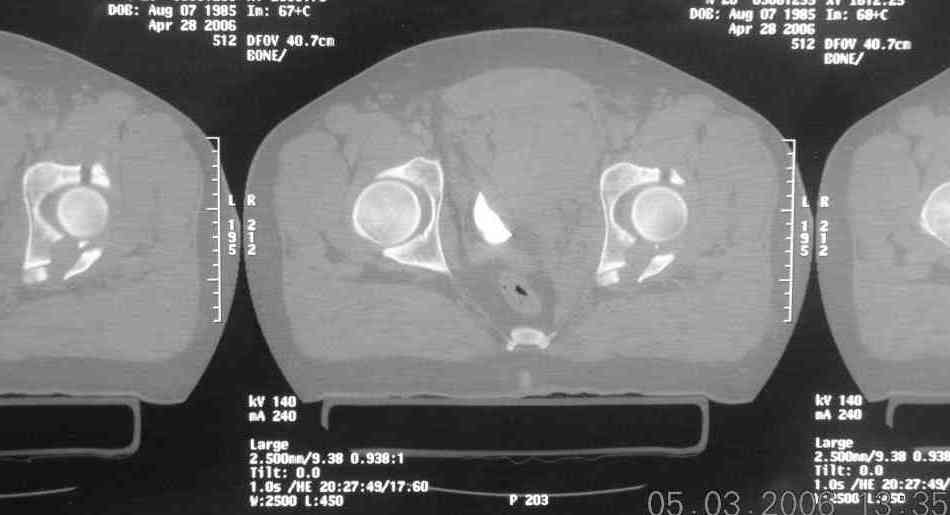

the case that I found is a 20yo male, MCC. his AP pelvis shows an interesting position of his bladder. it is pushed aside by a hematoma from SGA injury. we did a limited lateral window approach for the anterior column first, pt bumped up/supine. then closed and repositioned for KL. I could not find intra-op photos of cases when we did only a small incision for the AC screw (but they do exist!!). the lateral window is available for reduction assessment if a KL approach is being used. in the lateral position this window is available. the prone position definitely takes pressure off of the post column and facilitates reduction. in the lateral position a schantz pin in the ischial tub +/- bone hook in sciatic notch helps with PC reduction. the lateral position also gives better airway access for anesthesia. airway problems are rare, but prone position seems to be a bit more of a challenge to exchange the tube, or reintubate altogether. just something further to debate!